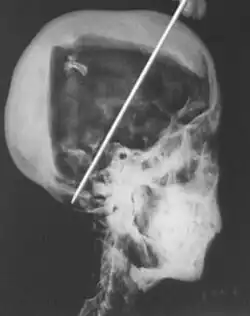

In 1968 R. G. Harrison, a professor of anatomy, used a portable X-ray machine to re-examine the mummy of Tutankhamun. Harrison quickly discovered that Carter had dismembered the mummy, something that is not mentioned in his publication but visible in photographs of the unwrapping. The mummy, surrounded by cotton wool and secured by modern bandages, had deteriorated since last photographed by Carter's team in 1926. The beaded skull-cap had disappeared, as had most of the skin on the head. The eyes appeared to be wide open as the eyelids had been destroyed, and the ears were broken off. The ribs had been sawn off and the front of the king's chest, including sternum and clavicles, had been removed. Stray beads from the large beaded collar were seen scattered in the torso on the X-rays. The limbs had been moved and further disarticulated, with the left hand and thumb of the right hand found in the sand under the body, and some of the digits on the hands and feet missing.[80][58][81] Although not mentioned by Harrison, the king's penis was also missing.[81] The additional damage to the mummy and the removal of the skullcap and collar likely occurred during the Second World War,[58] and components suggested to be from the collar have since appeared on the antiquities market.[82]

The X-rays revealed two levels of resin inside the skull. One was introduced when the body was lying on its back, pooling at the back of the head; the other when the head was tilted far back, settling at the top of the skull. Also present in the skull cavity were small bone fragments which Harrison initially believed to be the result of the embalming process. The fact that skull fragments were discovered led many to assume the king was murdered by a blow to the head, but the X-ray could not support or discredit this theory. His age at death was again estimated to be around 18, with a projected height in life of 168.9 centimetres (5 ft 6.5 in).[80] Serological analysis undertaken by the same team determined that Tutankhamun and the KV55 mummy had the same blood group, further indicating a familial relationship.[83]